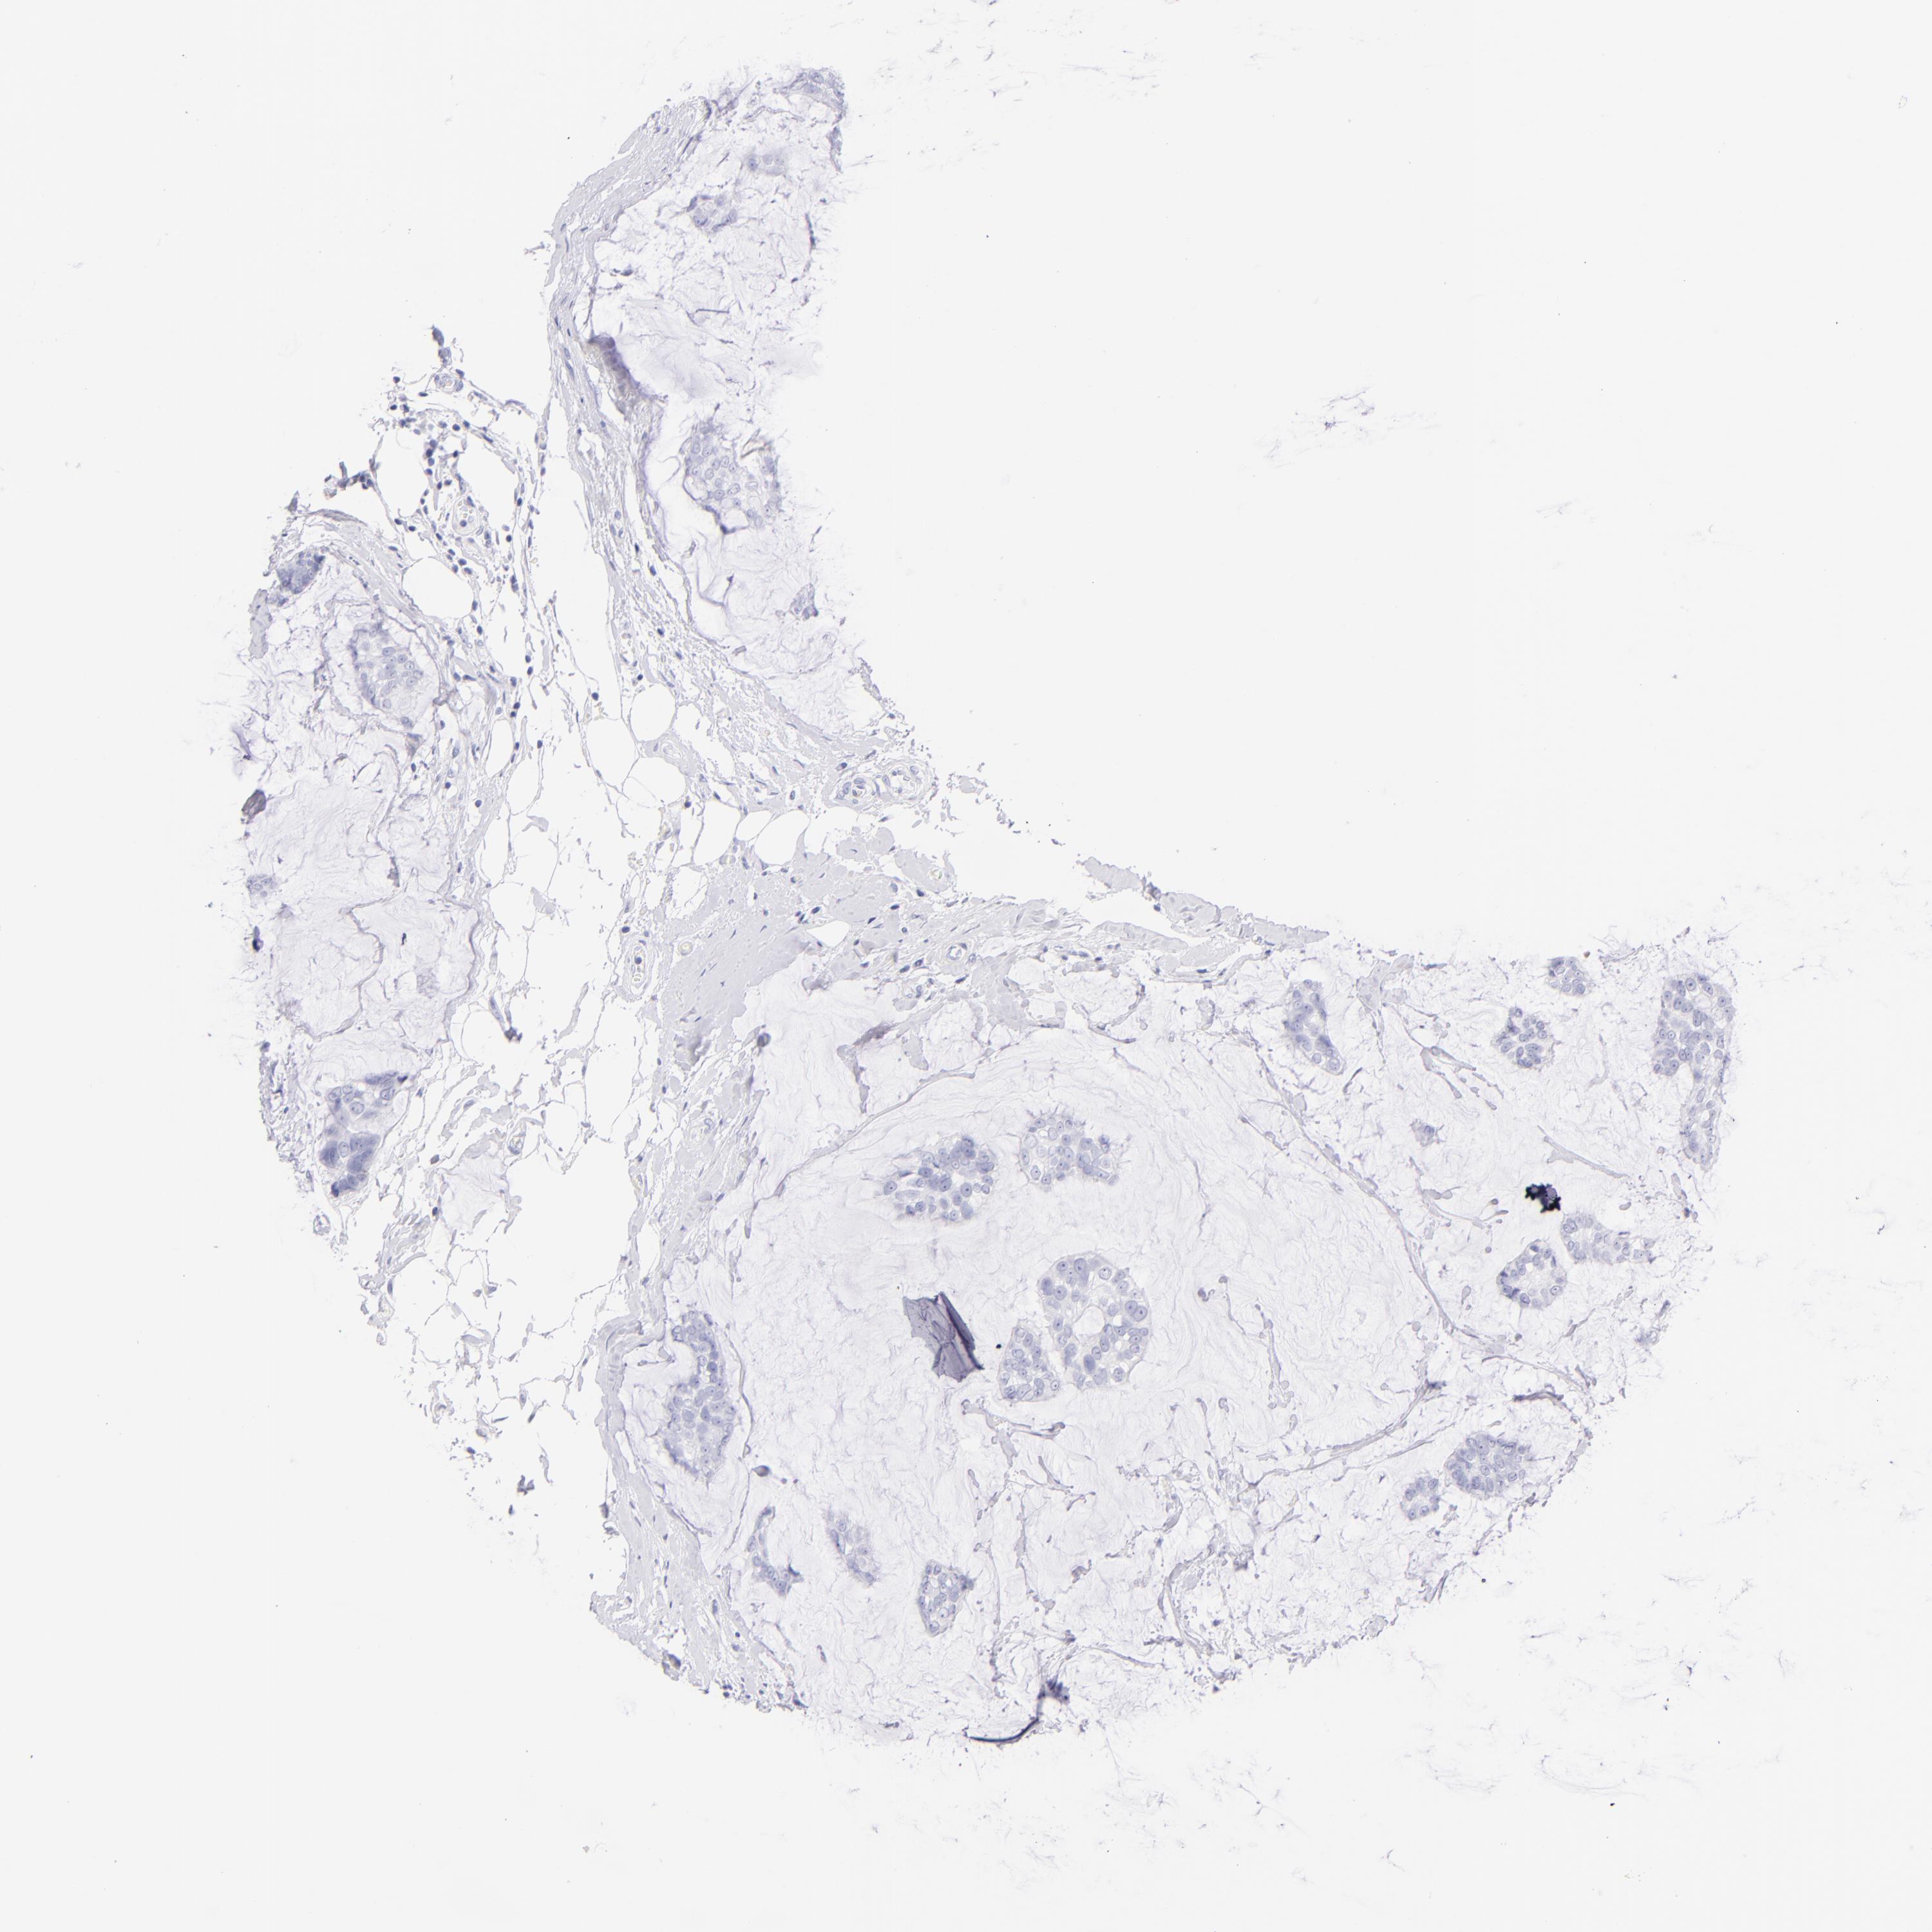

BRCA TCGA BRCA VALIDATION PROTEIN EXPRESSION

ANTIBODIES

AND

VALIDATION